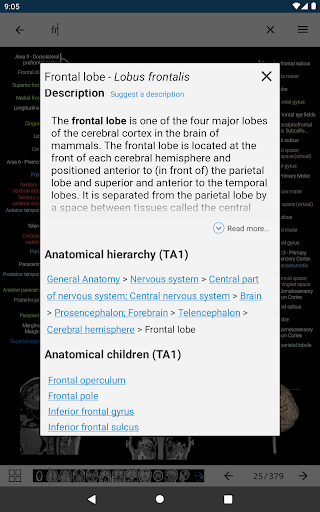

*Improved visibility of anatomical parts definitions

*Browse between anatomical parts using description links

-In the details view of an anatomical structure related terms are now displayed

-New module: Anatomical atlas of the lumbar spine on a CT, intervertebral discs and lumbosacral hinge in axial, coronal, and sagittal sections, and on 3D images-German is now supported for anatomical structures-Updated search mode (two new buttons in details view of a structure and a close button next to the searched structure label)-Fix search error on some Android versions-Fixed small bugs

-New module: Anatomical atlas of the lumbar spine on a CT, intervertebral discs and lumbosacral hinge in axial, coronal, and sagittal sections, and on 3D images-German is now supported for anatomical structures-Updated search mode (two new buttons in details view of a structure and a close button next to the searched structure label)-Fixed small bugs